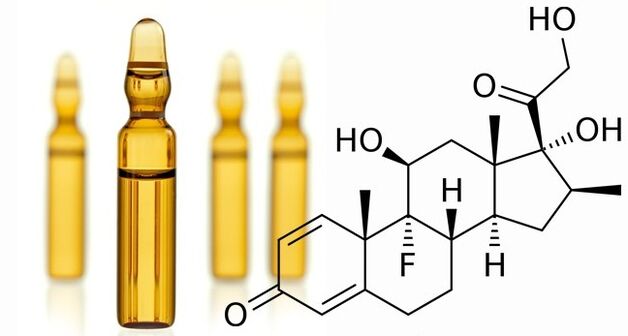

Injekcia

Ak je diagnostikovaná artróza kolenného kĺbu, liečba zahŕňa použitie intraartikulárnych intramuskulárnych injekcií. Injekcie na artrózu kolenného kĺbu sa intramuskulárne používajú na zavedenie glukokortikoidov. Sú potrebné na to, aby mali protizápalový účinok. Lieky znižujú bolesť, eliminujú opuch, červená derma. Používanie hormónov vo forme injekcií je povolené iba 2 až 3 krát ročne.